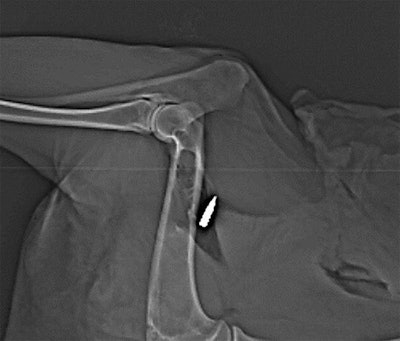

Gascho and colleagues thus set out to test the viability of using DECT to examine various kinds of bullets embedded in an animal cadaver: eight steel-jacketed lead bullets, four brass-jacketed lead bullets, and four solid bullets consisting of a copper-zinc alloy. Only the steel-jacketed bullets were ferromagnetic (AJR, September 2019, Vol. 213:3, pp. W105-W113).

They used various combinations of tube voltages to scan the bullets multiple times with DECT; the bullets were positioned both near and far from bone and in two different directional orientations. Next, they applied the extended CT scale algorithm to the imaging data to obtain more detailed image reconstructions of the bullets. Finally, they calculated the dual-energy index of the bullets using three different voltage pairs: 80 kVp and 140 kVp, 100 kVp and 140 kVp, and 120 kVp and 140 kVp.

After analyzing the data, the researchers found that DECT was able to discern differences between the lead bullets and copper-zinc bullets, regardless of the type of jacket surrounding the bullet. The copper-zinc bullets had higher average and peak dual-energy indexes than the lead bullets by a statistically significant degree (p < 0.01). Gascho and colleagues determined that the best dual-energy pair to distinguish the different types of bullets was 120 kVp and 140 kVp.